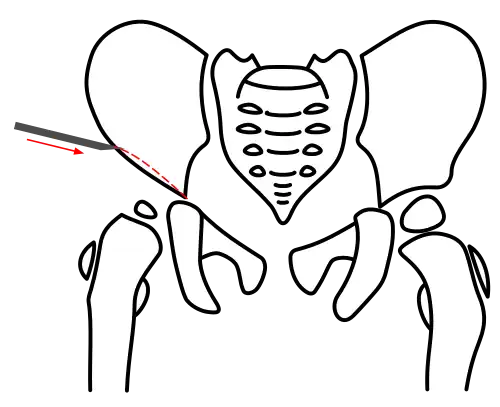

Acetabuloplasty leverages the open Y-suture. The ilium is cut above the acetabulum (osteotomy) to allow the lateral acetabular rim to be tilted downward, with the Y-suture serving as the pivot point. This principle underlies all acetabuloplasty techniques, with variations only in their execution.[4]

All osteotomy techniques require only a small incision between the groin fold and iliac crest. The muscles are bluntly separated to expose the ilium. The periosteum is detached just above the acetabulum, and the iliac bone is laid bare.[4]

In the Pemberton technique, under continuous X-ray guidance, the ilium is notched approximately 5 mm above the acetabular rim using a flat chisel, and the osteotomy is extended toward the Y-shaped physis. The acetabular fragment is then tilted downward and forward under X-ray control to achieve anatomical reconstruction.[7][10]